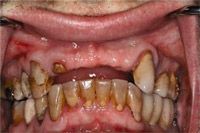

FIGS. 1-4 Clinical view of maxillary arch showing missing teeth (Fig. 1). Axial view showing planned implants in area 8, 9, 10, 12 (Fig. 2). Cross-sectional view showing buccal and lingual bone for implant placement (Fig. 3). Periapical view showing spacing of implants post placement (Fig. 4).

When a patient presents edentulous in the anterior region, a CT is needed to ascertain the present bone height and width, implant spacing and relative position to the adjacent teeth. Figure 1 shows how a patient presented, edentulous in areas number 8, 9, 10 and 12.